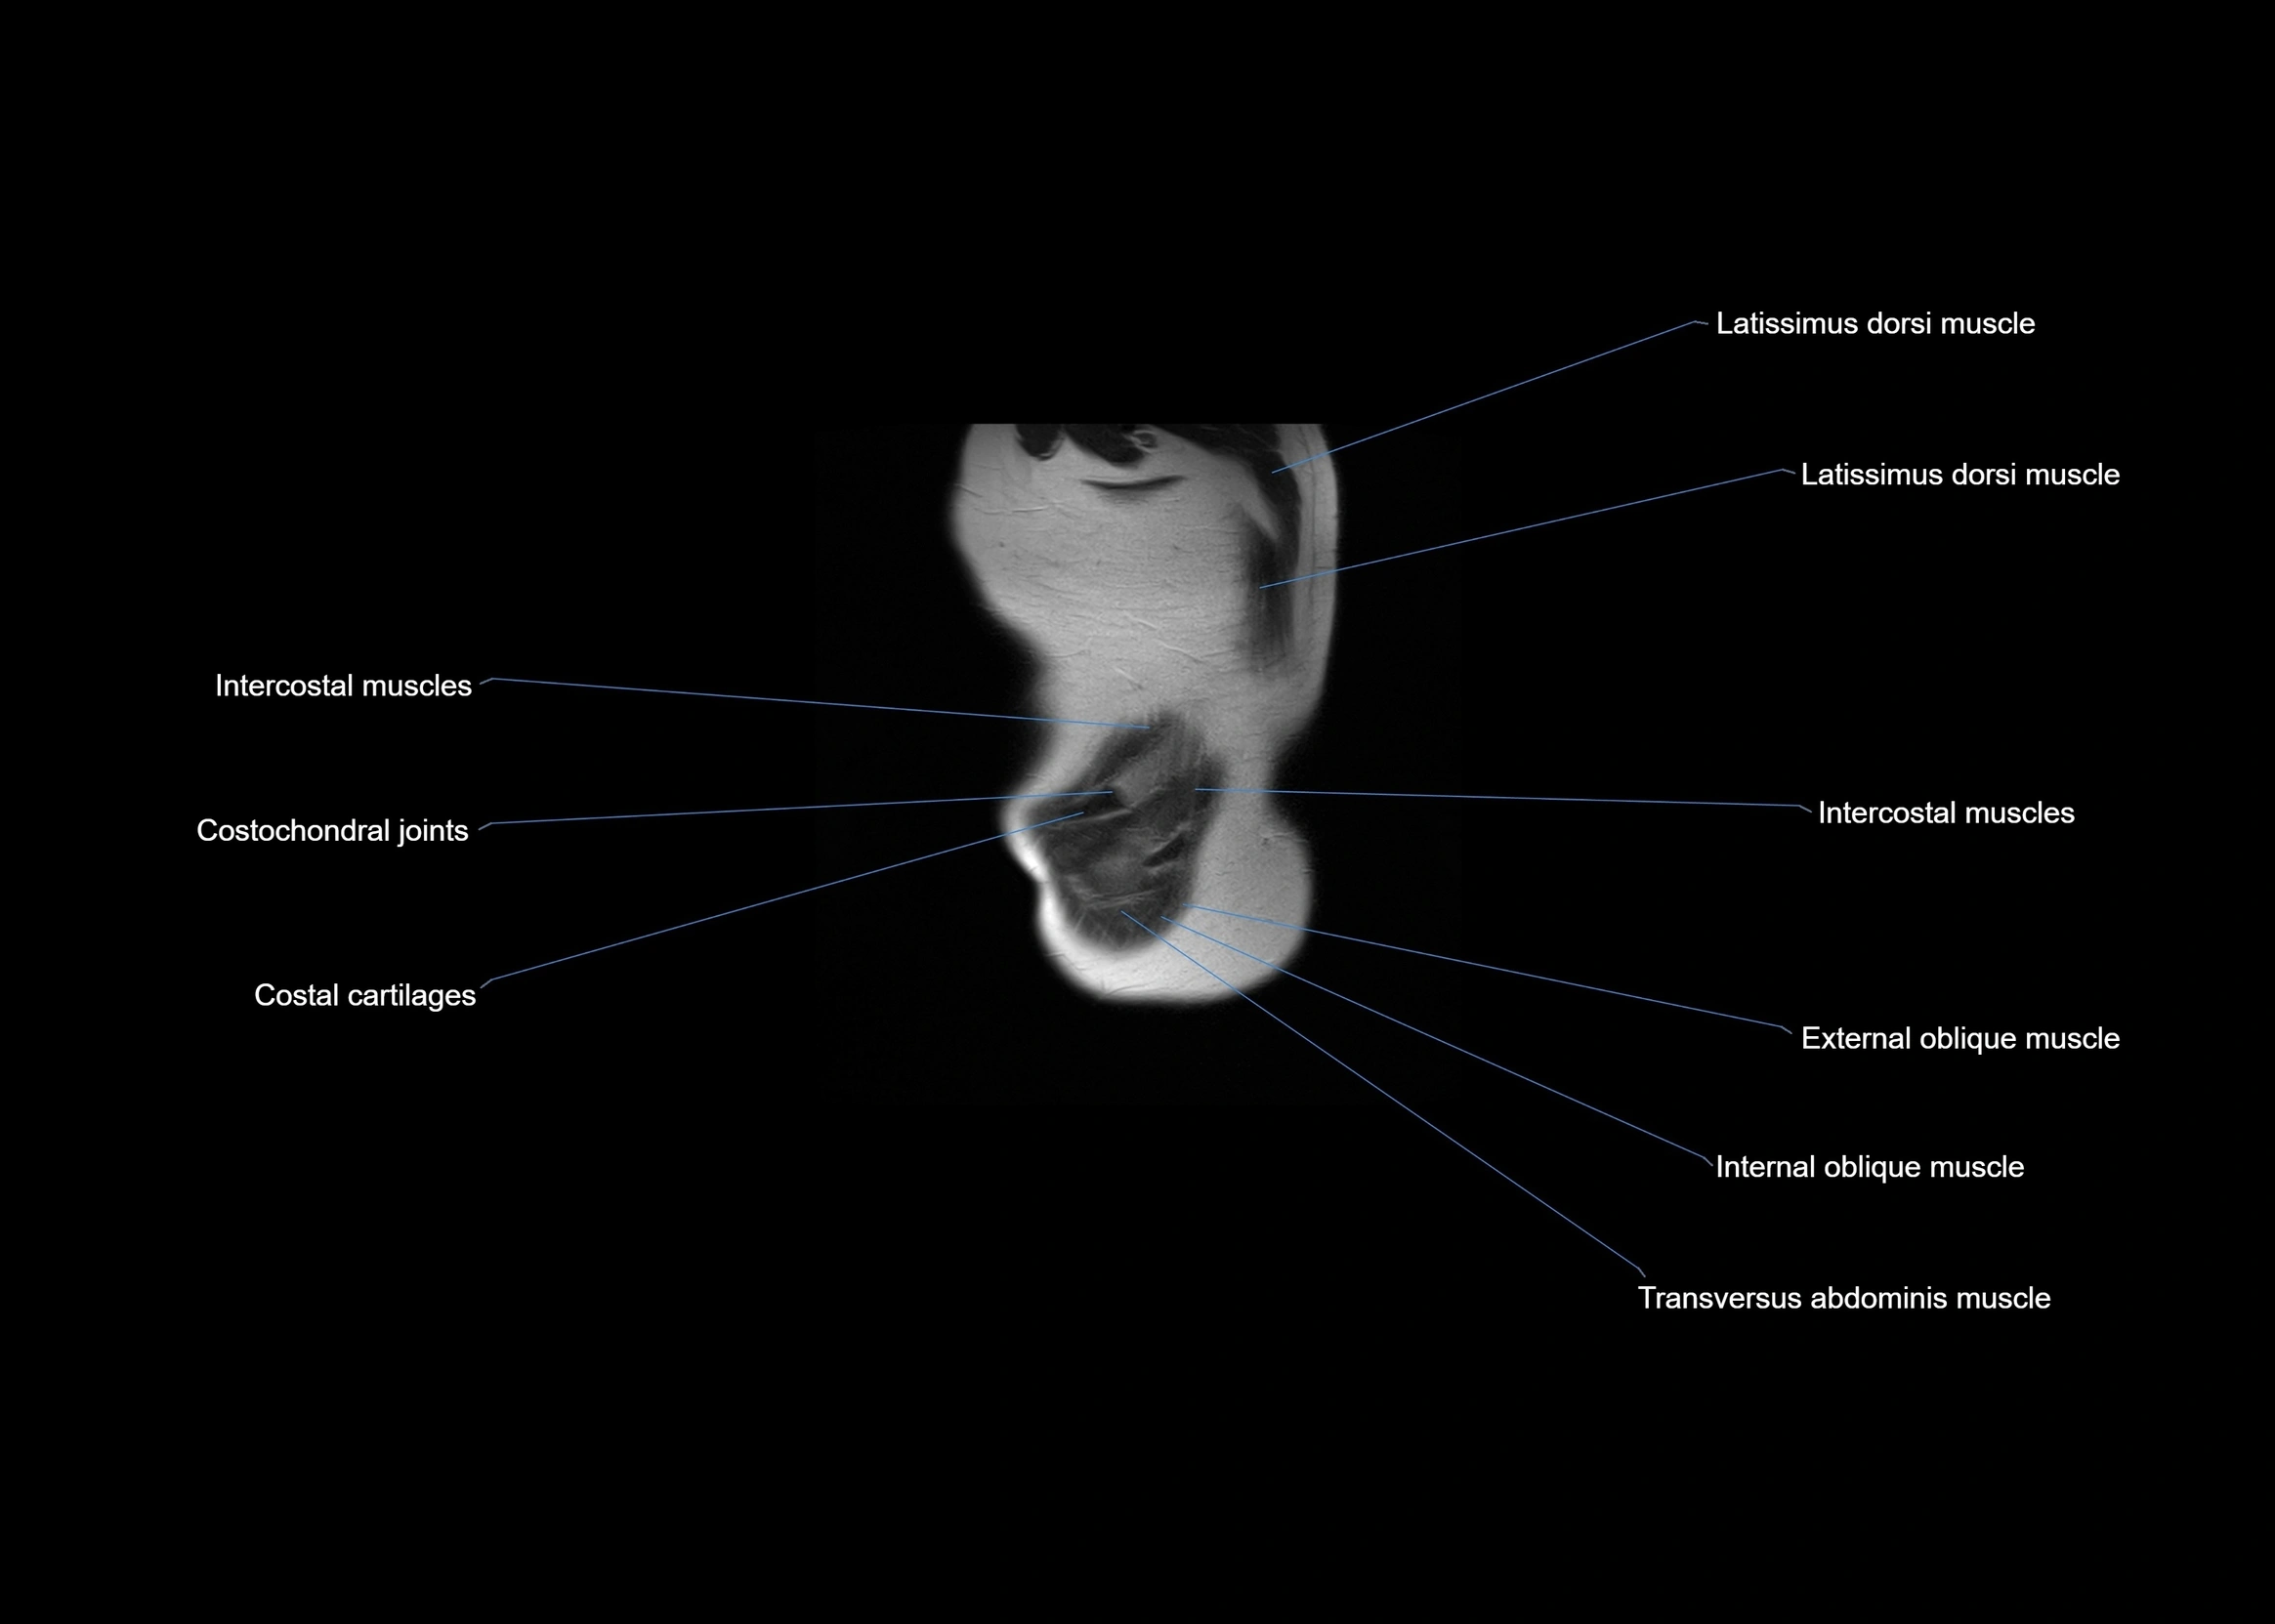

- Intercostal muscles

- Latissimus dorsi muscle

- Costochondral joints

- Transversus abdominis muscle